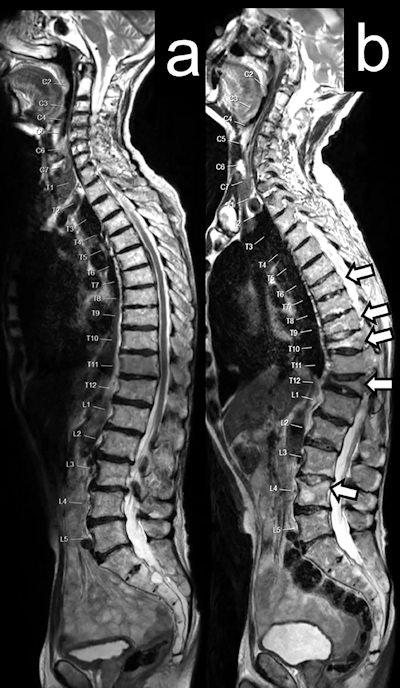

Patients were randomized to one of two dose levels with radium-223, 55 or 88 kBq/kg. To assess fractures, whole-body MRI scans were done at baseline, at cycle 2 and 4, and at one month post-treatment. During the follow-up period, patients were evaluated every four months for one year, following which, imaging was done according to routine clinical practice and scans were collected and reviewed centrally.

In total, 205 imaging scans in patients after they started radium-223 treatment were evaluated. Overall, 74 new fractures were identified in 20 (56%) patients on the MRI scans. Freedom from fracture was 79% at six months and 56% at 12 months, while the median time to first new fracture was 13.6 months.

Most new fractures developed within the axial skeleton. Out of all fractures, 50 occurred at a site of uninvolved bone. Of the 20 patients who had new fractures, 10 had symptomatic fractures, four had asymptomatic fractures, and six had uncertain symptomatic status.